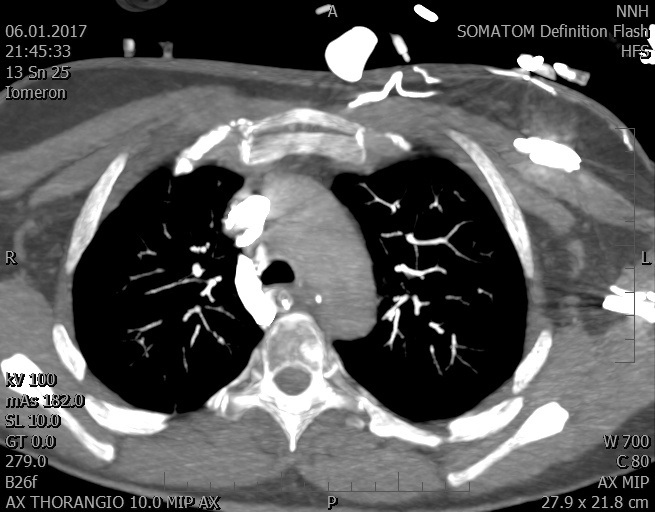

Video 1 - Akutní koronarografie prokázala normální nález na věnčitých tepnách s výjimkou suspekce na lehký spasmus na pravé koronární tepně.Echokardiograficky byla zjištěna těžká dysfunkce dilatované levé komory s nezvětšenou pravou komorou (video 2).

Video 2 - Echokardiograficky byla zjištěna těžká dysfunkce dilatační levé komory s nezvětšenou pravou komorou.Pro nejasnou příčinu zástavy jsme provedli i vyšetření výpočetní tomografií (CT), které vyloučilo plicní embolizaci (série 1 - soubory na konci článku). V den přijetí při přetrvávající oběhové nestabilitě byla nemocná opakovaně defibrilována pro fibrilaci komor se stabilizací rytmu po podání amiodaronu a mesocainu. Dle hemodynamických měření se jednalo o těžký kombinovaný šok. Vstupní laboratorní vyšetření bylo bez větších pozoruhodností. Posléze jsme doplnili anamnézu od příbuzných a zjistili, že pacientka užila do dvou hodin před srdeční zástavou první tabletu amoxicilinu na lehký respirační infekt. Při nevýtěžnosti vstupních vyšetření a nových anamnestických informacích jsme doplnili 14 hodin po kolapsu vyšetření koncentrace tryptázy v séru, která byla extrémně zvýšena (tabulka 2), což nás vedlo k podezření na anafylaxi.